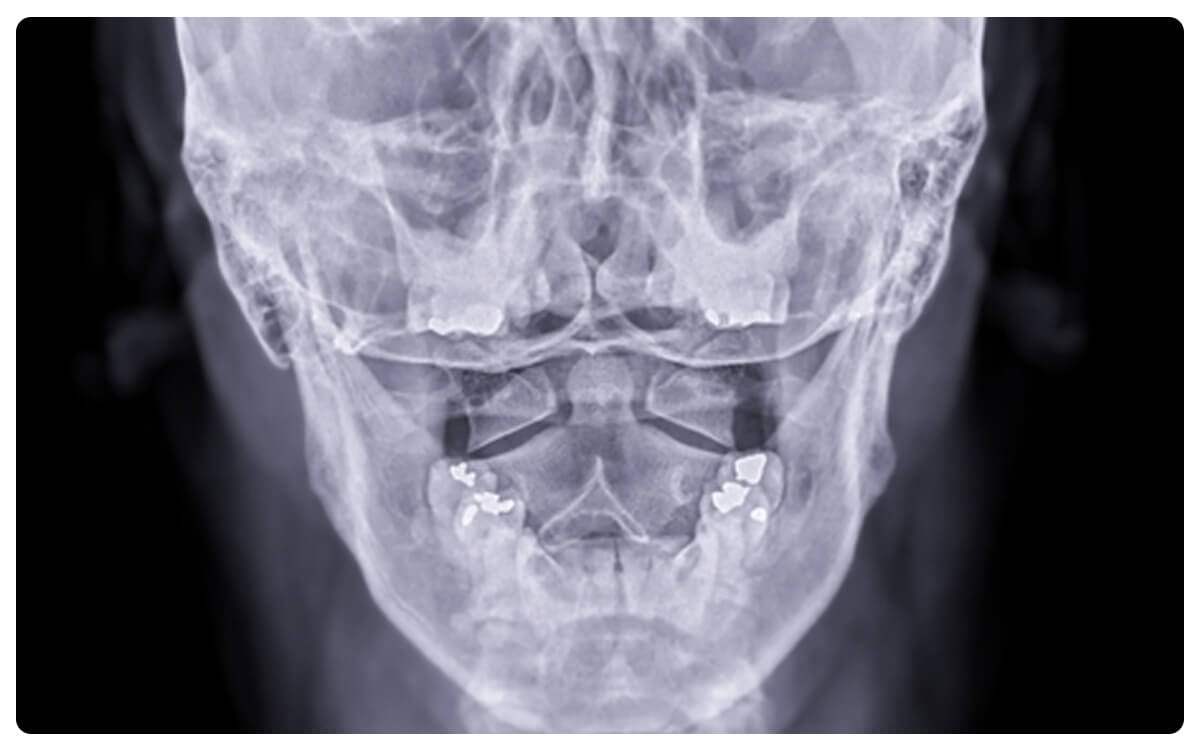

La Radiografía de Columna Cervical en posición de Boca Abierta se destaca como una técnica esencial en la radiología diagnóstica, proporcionando una visión detallada y específica de las vértebras cervicales superiores. Mediante la emisión controlada de radiación, esta técnica no invasiva permite capturar imágenes bidimensionales de la articulación atlantoaxial, ubicada en la base del cráneo.

La Radiografía de Columna Cervical en posición de boca abierta desempeña un papel crucial en la evaluación de condiciones como inestabilidad, subluxación y otras anomalías que afectan esta área anatómica, brindando información valiosa para la toma de decisiones clínicas informadas y el tratamiento adecuado de las afecciones cervicales.